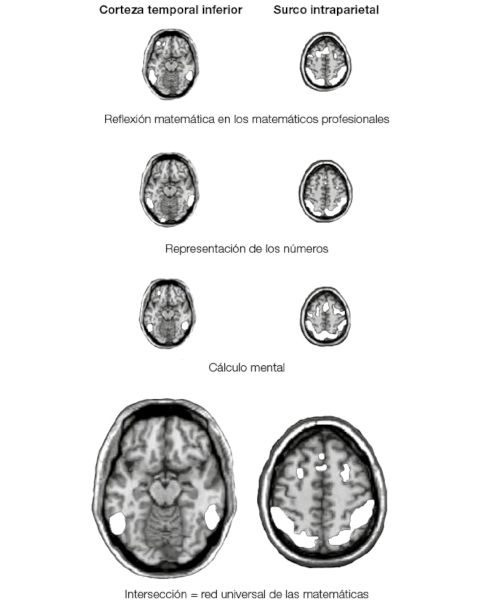

Conocerán a Emmanuel Giroux, ciego desde los 11 años, eximio matemático especializado en geometría. Parafraseando al zorro de El Principito de Saint-Exupéry, Emmanuel afirma convencido: “En geometría, lo esencial es invisible a los ojos; solo se puede ver bien con la mente”. ¿Cómo llega este hombre ciego a pasearse ágilmente por los abstractos espacios de la geometría algebraica, a manipular planos, esferas y poliedros, sin haberlos visto siquiera una vez? Descubriremos que utiliza los mismos circuitos cerebrales que otros matemáticos, con la única salvedad de que su corteza visual, lejos de permanecer inactiva, se recicló también para hacer matemáticas.